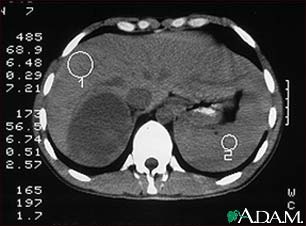

Adrenal Tumor - CT

CT scan of the upper abdomen in a person with a right adrenal mass. The adrenal glands are located above the kidneys.